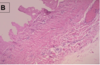

what do we see in the picture?

what is the definition of what is in the picture?

ulcer

discontinuity of lining epithelium, tissue necrosis, and resultant inflammation

what is this picture?

Ulcer

Micro: note discontinuity in epithelial lining. Ulcer.